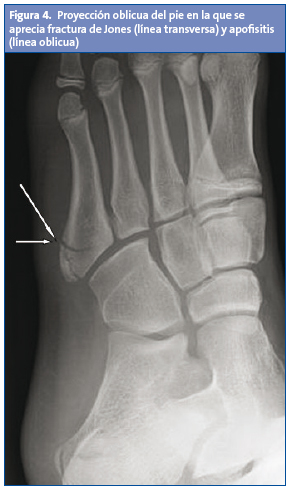

Se revisan la clínica y el diagnóstico radiológico, destacando la importancia de la proyección oblicua, para la mejor visualización del centro de osificación, y de la radiología bilateral comparativa. Las líneas de fractura suelen ser transversas al eje metafisodiafisario del quinto metatarsiano, mientras que en la enfermedad de Iselin la afectación del núcleo de osificación suele ser oblicua a dicho eje.

Radiológicamente, estas fracturas suelen presentar una línea transversa al eje metafisodiafisario del quinto metatarsiano, mientras que en la enfermedad de Iselin la imagen de la apófisis es oblicua a dicho eje (Fig. 4).